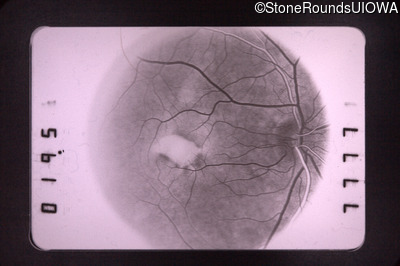

Fluorescein Angiography - Right - 20/40 -2

Exemplar